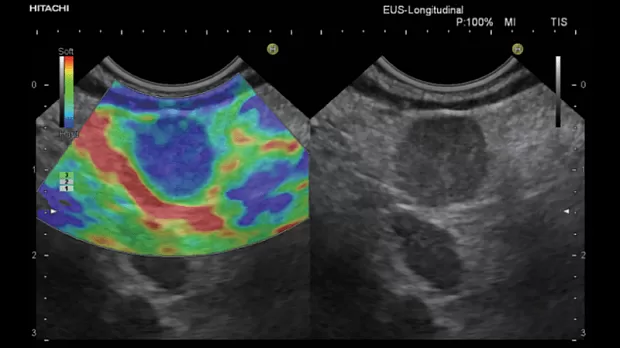

Для оценки лимфоузла изпользуется визуальная цветовая шкала , где :

• однородный зеленый цвет – нормальная ткань ЛУ

• однородный синий рисунок - злокачественная ( жесткая ) ткань

• красный и желтый – соединительная ткань и сосуды

Функцией эластографии оснащены эндоскопические ультразвуковые станции Hitachi и Olympus EU ME-2. Выполняется при помощи ЭХО-эндоскопов ( эндобронхиальных и гастроинтестинальных).